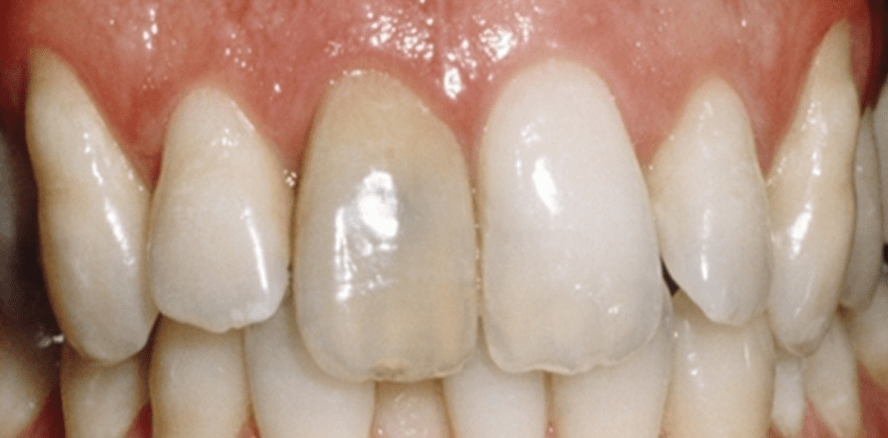

Mit einer endodontischen Behandlung geht oftmals eine Beeinträchtigung der Zahnästhetik einher. Devitale und wurzelbehandelte Zähne verfärben. Vor allem im Frontzahnbereich können die sogenannten grauen oder schwarzen Zähne störend wirken. Wünscht sich der Patient die Wiederherstellung der ursprünglichen Zahnfarbe, bieten sich dem Zahnarzt verschiedene Möglichkeiten, die sich vor allem in Hinsicht auf ihre Invasivität unterscheiden.

Foto: © Ultradent Products